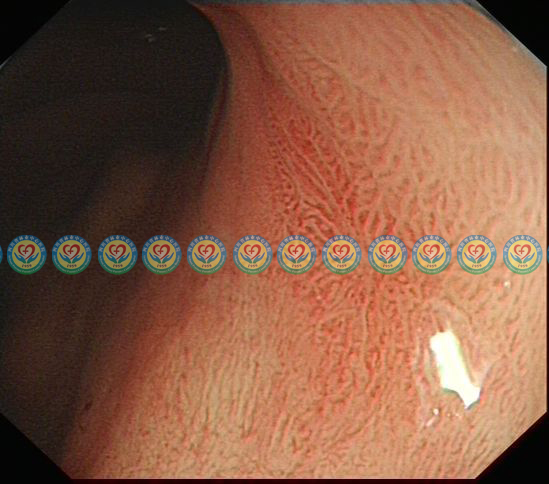

精查胃镜,靠近病变,弱放大观察粘膜表面腺管结构